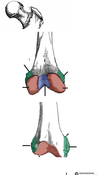

Grey turner’s

Flank ecchymoses

Cullen’s

Periumbilical ecchymosis (tracks up falciform)

Grey Turner’s sign

Flank ecchymosis

Acute pancreatitis

Cullens sign

Peri-umbilical ecchymosis